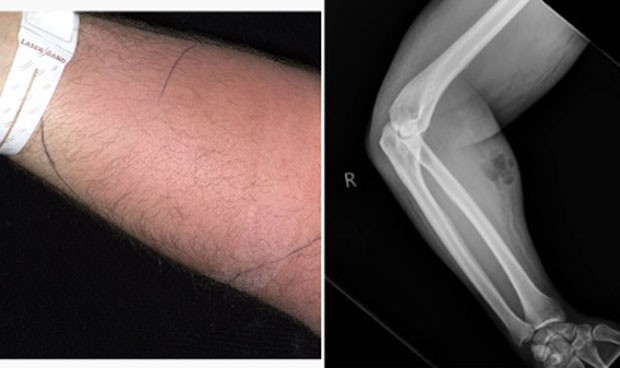

Imagen de la infección del paciente que se inyectó semen en el brazo.

Según ha confesado Alejandro Macías (@doctormacias en Twitter), el hombre en cuestión se había dedicado a ‘pincharse’ su propio semen para tratar este dolor que se siente en la región lumbar. Acompañado de varias fotografías, que fueron difundidas por la publicación Irish Medical Journal, se pueden ver las extremidades del afectado.

El facultativo ha explicado que este ‘ritual’ le ha provocado al hombre una “extensa infección del brazo” y que en la radiografía se llega a ver el gas que producen las bacterias.